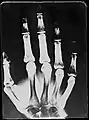

The fact that a certain density of a photographic layer has been caused by a specific amount of actinic radiation (visual light, UV-light, X-Rays, autoradiography, etc.) can be used to qualify and perform spatial measurements of a physical phenomenon. A calibrated photographic process is used to obtain quantitative measurements as well.